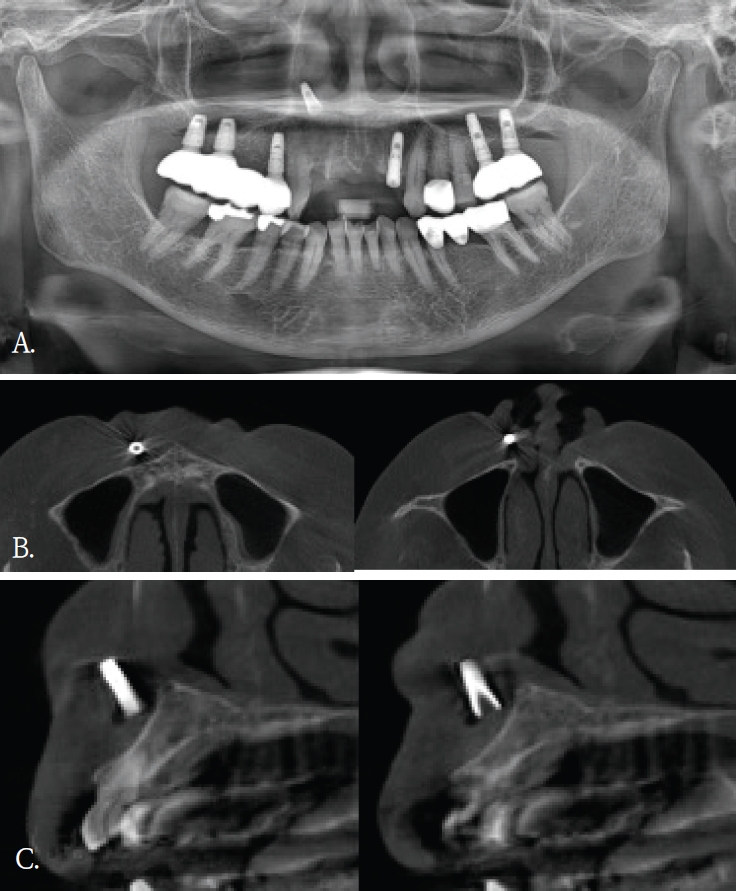

임플란트 식립 중 식립체가 시야에서 소실되어 위치 확인을 위해 60대 여자환자에서 파노라마방사선검사를 시행하였다. 파노라마방사선영상에서 임플란트 식립체로 추정되는 금속성 방사선불투과성 구조물이 우측 비강 부위에 중첩되어 관찰되었고 영상에서 비강 하연 부근에 위치한 것처럼 보였다(Fig. 4A). 이에 비강 및 상악 치조골과의 정확한 위치 관계를 평가하기 위해 콘빔CT 검사를 시행하였다. 콘빔CT에서 해당 구조물은 고음영 금속성 구조물로 확인되었으며, 상악 우측 전치부 측와 부위의 순측 연조직에서 관찰되었다(Figs. 4B and C). 또한 비강저 및 상악 치조골 피질골의 연속성이 보존되어 구조 발치와가 관찰되었다(Fig. 5A). 이러한 소견은 좌측 상악동 점막의 염증성 변화 가능성을 시사하였다. 상악동 병변의 범위 및 발치와와 상악동하연의 관계를 평가하기 위해 콘빔CT검사를 시행하였다. 콘빔CT에서 좌측 상악동 내에 연조직음영에 의한 혼탁이 관찰되었으며, 이는 상악동의 약2/3이상을 채우는 양상이었고 상악동 소공주변까지 연장되어 보였다. 또한, 상악동 전하방에서 경계가 명확한 작은 타원형의 균질한 고음영 구조물이 관찰되었으며, 골밀도에 해당하는 방사선불투과성 이물질로 판단되었다(Figs. 5B and C). 해당 고음영 소견은 파노라마방사선영상에서는 명확히 구분되지 않았다. 환자의 발치 병력을 고려할 때 해당 구조물은 상악동 내로 이동한 잔존치근이 의심되었으며, 외과적 제거를 시행하였다. 제거된 이물질은 상악동 내 잔존 치근으로 확인되었다.

A. Panoramic radiograph shows an implant-shaped foreign body superior to the maxillary anterior region and appearing superimposed on the nasal cavity. B. Axial cone-beam computed tomographic (CBCT) image demonstrates that the foreign body is located in the labial soft tissue, without involvement of the nasal cavity. C. Cross-sectional CBCT image demonstrates that the foreign body is located in the labial soft tissue rather than in the maxillary anterior alveolar bone.

A. Panoramic radiograph. An extraction socket of the left maxillary first molar is noted. Diffuse haziness of the left maxillary sinus is observed; no other definite abnormality is identified. B. Panoramic reconstruction, C. cross-sectional cone-beam computed tomographic images. Soft-tissue density nearly fills the left maxillary sinus. A small radiopaque foreign body is identified at the floor of the sinus.

증례 5와 같이 파노라마방사선영상에서 모호하게 관찰되었거나 증례 3과 4같이 파노라마방사선영상에서 협-설위치를 명확하게 알 수 없었던 경우, 콘빔CT영상에서 임상적으로 의미있는 이물질임을 확인되었고 외과적 치료가 시행되었던 증례들이다. 특히, 이들 소견은 악골이 아닌 안면 연조직 부위에서 관찰되어, 주의 깊은 영상판독의 중요성을 다시금 일깨워 준다.